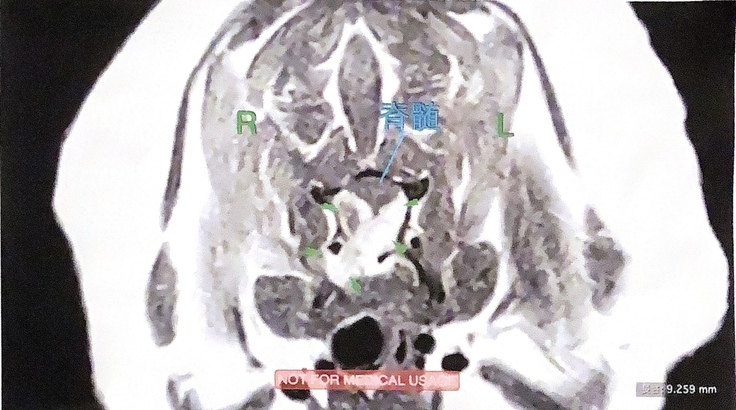

夜間救急にすぐに連れて行きレントゲン撮影をしてもらいましたが、原因は不明でした。翌日かかりつけ医に朝一番で行って診察してもらいましたが、頸椎ヘルニアの可能性があると言われMRI撮影が必要とされました。浜松市ではすぐに撮影してくれる病院はなく、静岡県島田市に撮影をしてくれる病院を探し出し検査後、

首の6番の骨が癌に侵されて骨が変形してしまい神経を圧迫していると

膝から崩れ落ちてしまう程の診断を聞かされました。何もしなければ余命3ヵ月と宣告されました。足に麻痺が出て自らの意思で排尿することができなくなりそれからずっと麻痺したままです。時々ですが、うれしい時には後ろ脚が少しだけ、動きます、頭部にはダメ-ジがないため表情はまだ豊です。これが又、すごく切なく、何とかしなくては!という思いななりました

頸椎C6のMRIです。

地元の病院では手術していただける病院がなくMRI撮影をしていただいた病院で

岐阜大学動物病院神経科を紹介していただきました。岐阜大学動物病院での診断は下記の画像になります。手術はリスクが高すぎしない方が良いとの事です。治療方針は、放射線治療により、癌の縮小、神経の圧迫解除による、自立歩行、排尿、排便を目指し。出来る限りの延命をめざします、

神経に浸潤した、癌と骨は手術で取り除く事は、極めて難しく、、、